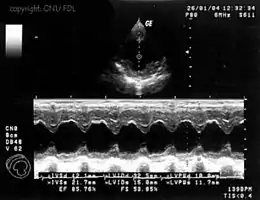

Outros métodos de imagem de ultrassom incluem movimento ou modo M, que pode ser usado para observar o batimento do coração como uma função do tempo.

Um plot da intensidade do eco versus o tempo é chamado um scan A. Para formar uma imagem bidimensional, é necessário scanear em muitas direções (colunas da planilha) diferentes. Em um scan B, o brilho da tela corresponde à intensidade do eco, plotado versus posição no corpo no plano do escaneamento. O transdutor do scan B envia um feixe estreito dentro do corpo. A intensidade do eco determina a cor que a célula vai ter (branco para um eco forte, preto para um muito fraco, e graduações de cinza para as intensidades intermédias). Quando ocorre a transição entre dois meios com grande diferença de impedâncias, maior será a intensidade do eco e, desse modo, mais intensa (branca) será a imagem gerada.